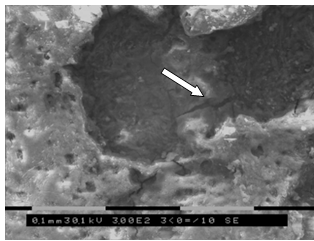

. Исследование морфологии огнестрельных переломов пластинчатых и

трубчатых костей методом сканирующей электронной микроскопии (50 образцов).